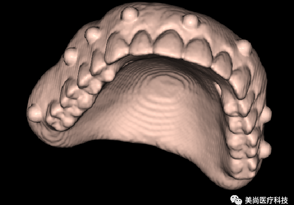

步骤:取模 → 灌制石膏模型 → 扫描仪扫描石膏模型 → 获取数据并保存

模型数据(口外模型扫描仪光学扫描、口内扫描仪直接扫描)